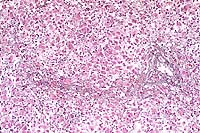

- In sections of both lobes of the thyroid gland, follicles

are small and lack colloid. Follicular epithelial cells are columnar

to polygonal and occasionally bilayered. The cytoplasm is eosinophilic,

abundant, and contains large, clear, poorly defined vacuoles.

Basal to central nuclei are large (up to 15 mm in diameter),

round and have coarsely stippled chromatin.

10x

obj

- Case14-1. Thyroid. There is diffuse follicular epithelial

hypertrophy and hyperplasia. Relatively few follicles have discernable

lumens or colloid production.